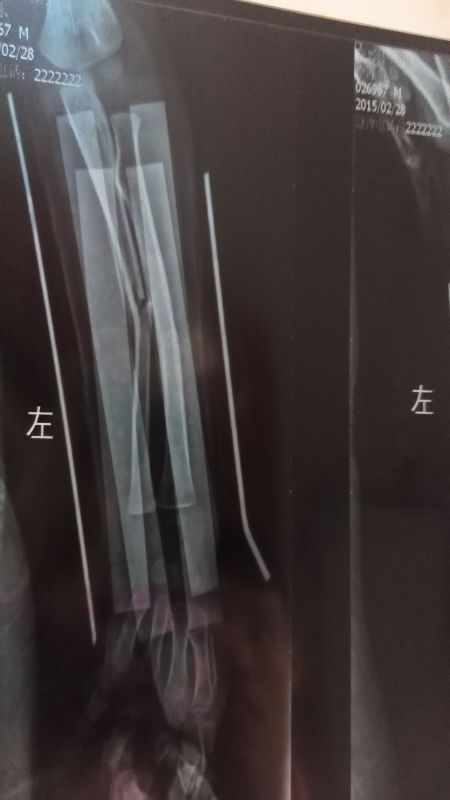

3岁小孩摔断手,医生接骨后的效果,请大侠帮忙看一下 点击展开 匿名用户 2015-02-28 15:50 为您推荐: 其他回答 根据你提供的图片看现在断端恢复的不是太好,一般是不要紧的,等孩子大一点就可以了 ҽĴ 2015-02-28 15:54 相关问题 老公手骨折,医生开了一个月的接骨七厘片,现在怀孕一个多月了,对胎儿有影响吗?很担心 我昨天摔住了,去查医生说小孩没事,今天孩子在肚子里不动了,有事没事 各位在线得医生,我想请问下,2岁四个月得小孩,一直记性不好,要给他吃什么好呢?好担心啊!谢谢告诉下